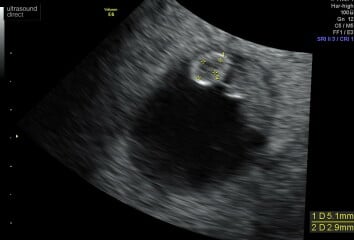

Hope your scan went well OP? This was mine yesterday 8+2, ended up as a transvaginal scan due to gas! It shows the baby (fuzzy gummy bear shape) and the yoke sack circular thing-I asked them to take measurements of the yoke sac because it can be a good indicator of prognosis. Can't seem to upload the video but as others said could see a flickering heartbeat. ❤️

8 Week Scan Experiences please